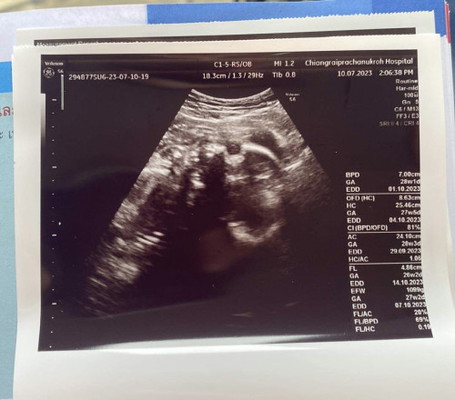

แต่ลูก 26w 2d หนัก 1,099 กรัม น้ำหนักปกติไหมค่ะ หรือน้อยไปค่ะ

น้องตามเกณกำลังสวยเลยคะ น้ำหนักแม่ลดไม่ใช้ว่าน้องจะลดตามนะคะ น้องจะเพิ่มขึ้นเรื่อยๆจนกว่าจะคลอดเลย